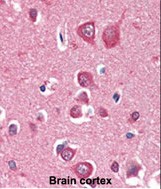

- Formalin-fixed and paraffin-embedded human Brain Cortex tissue reacted with PINK1 Monoclonal Antibody (Cat.#P30246), which was peroxidase-conjugated to the secondary antibody, followed by AEC staining. This data demonstrates the use of this antibody for immunohistochemistry; clinical relevance has not been evaluated.